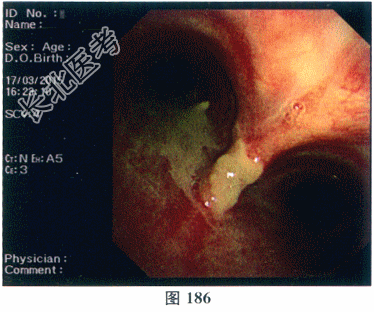

- 多项选择题3.[提示]患者纤维支气管镜检可见气管黏膜充血伴脓性分泌物,分泌物培养未发现曲霉菌及其他病原菌包括抗酸杆菌。黏膜活检病理检查: 增生的纤维组织呈慢性炎性改变,内见小灶增生的复层鳞状上皮; 抗酸染色(-)、PAS染色(-)。支气管灌洗液培养:未见曲霉菌生长, 大肠埃希菌(+),超广谱β-内酰胺酶(ESBL)阳性。免疫指标检测: ANA(+);核型1滴度1: 320,核型2滴度1: 100,抗干燥综合征抗体(SSA)阳性(+++)。胞质型ANCA(C-AN-CA)阳性。蛋白酶3型ANCA(PR3-ANCA)阳性(+++)。血清总IgE正常。纤维支气管镜检见图186、图187。目前该患者诊断为( )